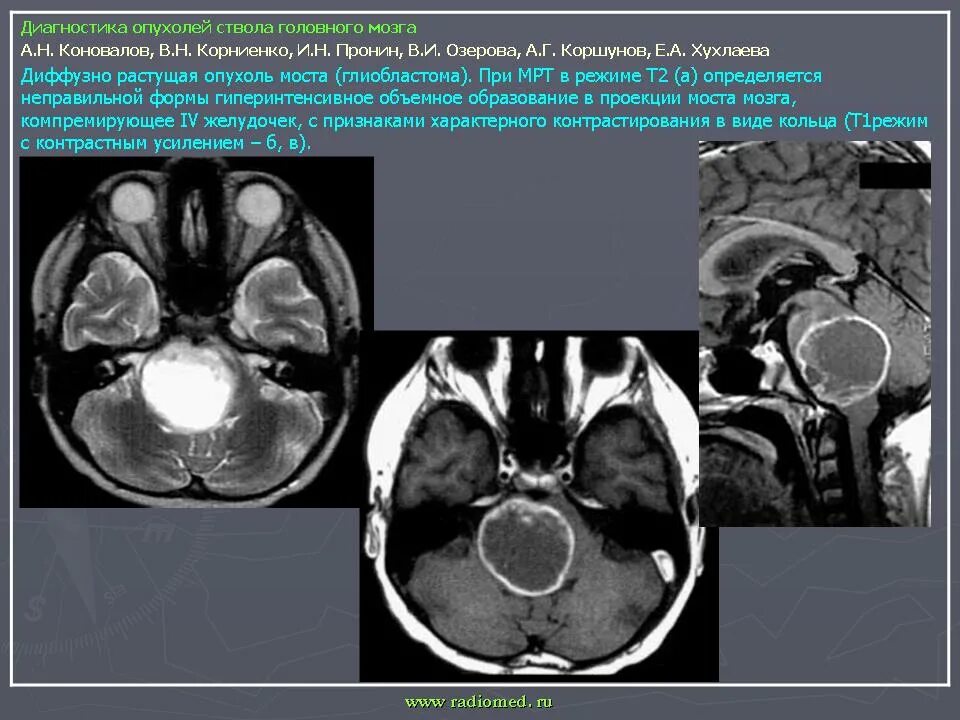

Сколько живут с доброкачественной опухолью головного мозга